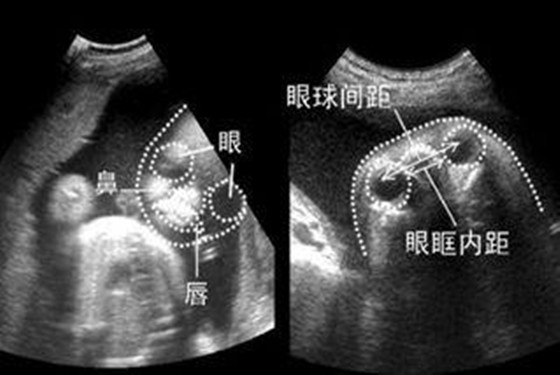

从以上怀孕五个月的胎儿彩超图可以看出,小宝宝的五官(分得出眉毛和眼睑的界线)和四肢(宝宝的手指和脚趾都已经长出了指甲)已经差不多发育成熟了,而且身体的各个器官(味觉,触觉,听觉,嗅觉)功能也在逐渐完善中,胎儿的性器官(生殖器)已经发育得非常明显了,此时通过B超检查完全能分辨出男孩女孩了。